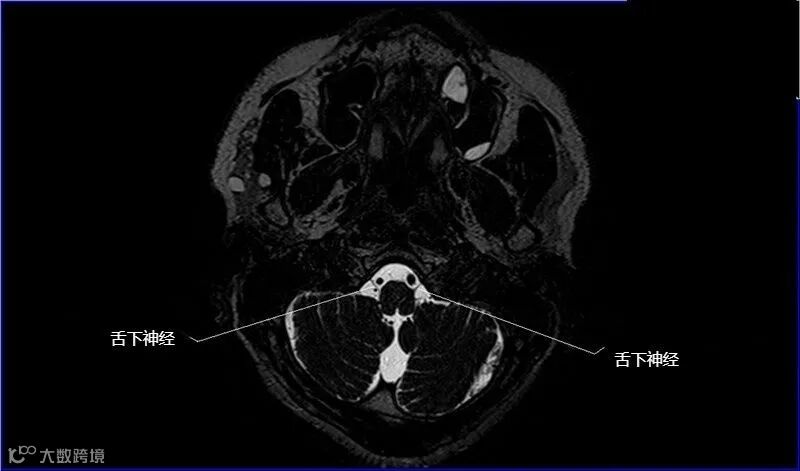

一嗅二视三动眼,四滑五叉六外展,

七面八听九舌咽,迷走及副舌下全。